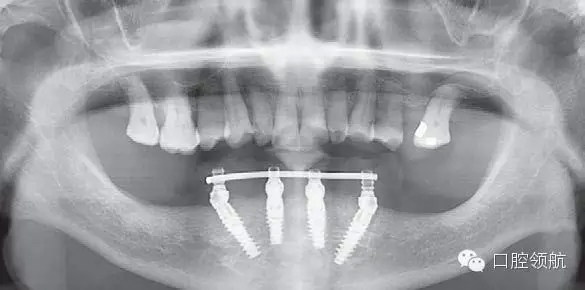

植入4顆NobelActive,后部為RP4.3*15,前部為RP4.3*13。安放閉口轉(zhuǎn)移桿(圖6-9,圖6-10)。

3.webp.jpg

圖6-9 術(shù)中拔除10顆患牙

4.webp.jpg

圖6-10 下頜植入All-on-4 后口內(nèi)照